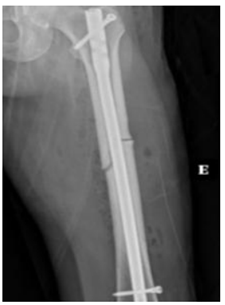

Você é residente da Clínica Médica e foi

acionado/a para realizar interconsulta de uma

paciente de 68 anos na Enfermaria de

Ortopedia, após fixação de fratura de fêmur.

Durante avaliação, paciente relata diagnóstico

de osteoporose, e está fazendo uso regular de

carbonato de cálcio, Vitamina D3 2000 UI/d e

alendronato há 11 anos. Quando inquirida, ela

nega quedas. Refere que estava realizando sua

caminhada matinal no Parque do Utinga,

quando sentiu uma dor intensa na face lateral

da perna esquerda, momento em que procurou

o Pronto Atendimento. Na avaliação bioquímica

complementar, ela apresenta 25OHD de 42

ng/dL, níveis de eletrólitos, albumina, PTH e

eletroforese de proteínas séricas normais. Após

procedimento ortopédico, apresenta a seguinte

radiografia:

Neste momento, a conduta prioritária é: